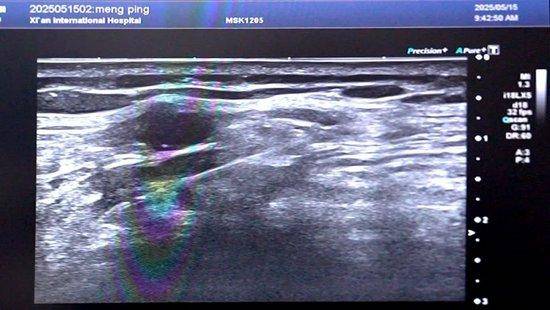

阳光讯(贺迪 记者 郑亚雷)三种强效止痛药仍无法缓解剧痛,当传统治疗方式“束手无策”时,一种创新的“点击+移动式”超声消融技术正在改写恶性胸膜间皮瘤患者的结局。 日前,中国超声医学工程学会会长、西安国